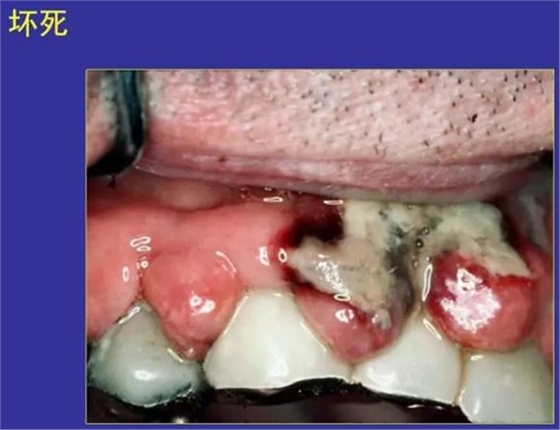

8.壞死:局部細胞的病理性死亡

壞疽:壞死又受到腐敗菌感染

見于壞死性口炎